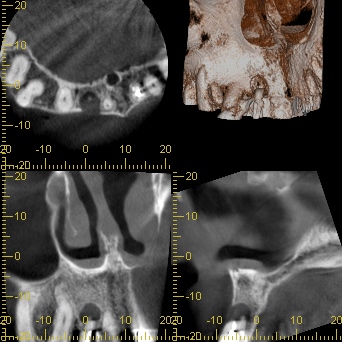

初診時レントゲン・CT

膿が大きく認められました。